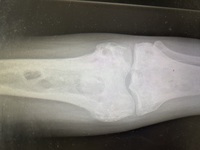

Lytic bone lesions with sclerosed margins 1

The patient also had complaints of multiple bone pains. X-Ray of lower limbs showed multiple lytic bone lesions with sclerosed margins.